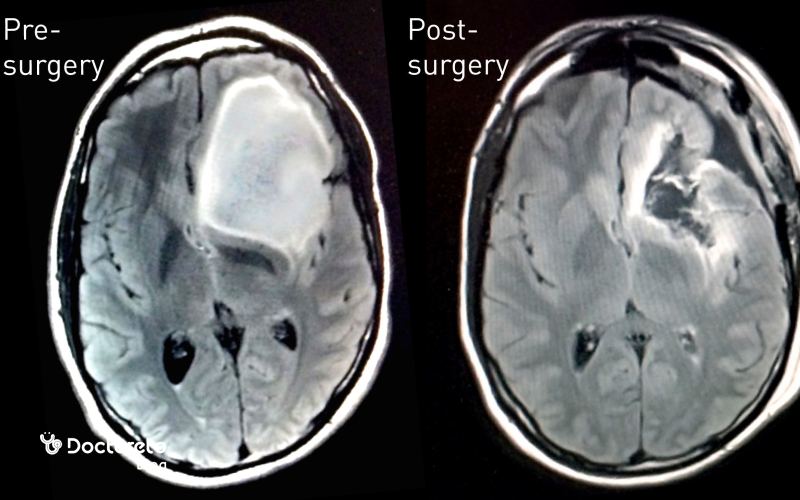

عکس تومور مغزی قبل و بعد از جراحی

عکسهای قبل از جراحی برای تعیین اندازه و محل دقیق تومور و برنامهریزی مسیر جراحی ضروری هستند. این تصاویر به جراح کمک میکنند تا حداقل آسیب به بافت سالم مغز را داشته باشند. بعد از جراحی، تصاویر MRI یا CT برای بررسی میزان برداشته شدن تومور و شناسایی هرگونه تومور باقیمانده استفاده میشوند. همچنین برای پیگیری روند بهبودی و پیشگیری از عود بیماری، این عکسها به صورت دورهای گرفته میشوند.

عکس تومور مغزی بدخیم ابزار مرکزی برای تشخیص، سنجش شدت درگیری و برنامهریزی درمان است. در مراحل اولیه، تصاویر معمولاً تودهای کوچک با تفاوت تراکم کم نسبت به بافت طبیعی را نشان میدهند و علائم میتواند خفیف باشد؛ در مراحل پیشرفته، توده بزرگتر و نامنظم است و فشار بر ساختارهای اطراف و تورم دیده میشود. امآرآی و سیتیاسکن امکان تعیین محل، اندازه و گسترش را فراهم میکنند و با مقایسهٔ دورهای میتوان اثر درمان و احتمال عود را ارزیابی کرد. تصاویر پیش و پس از جراحی نیز میزان برداشت تومور و نیاز به اقدامات بعدی را روشن میسازند. بدینترتیب، تصویربرداری منظم به تصمیمگیری دقیقتر کمک میکند.